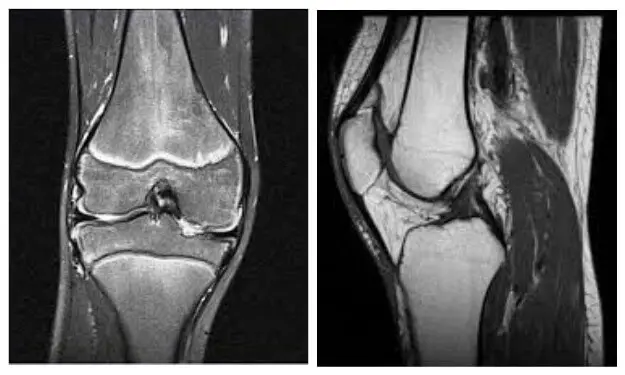

МРТ колінного суглоба

МРТ коліна дозволяє побачити такі зміни, як розрив або розшарування меніска, розрив або надрив (травму) зв’язок, травму хряща, запалення кістки і в підхрящевій пластині, запалення жирового тіла Гоффа та ін. МРТ колінного суглоба дозволяє побачити артрит (накопичення рідини в колінному суглобі).

Артроз при МРТ видно, але частіше для цього використовують рентген зважаючи на більшу інформативність при діагностиці артрозу коліна. Читати більше про показання, протипоказання і що можна обстежити в колінному суглобі.